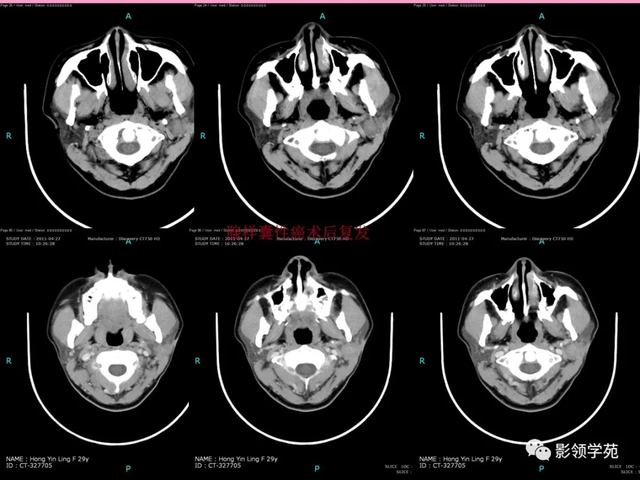

病例1:男性, 41岁,因“发现右耳垂下肿物1月余”:

病理:混淆瘤

病例2:女,30岁,发现右耳垂下肿物9月